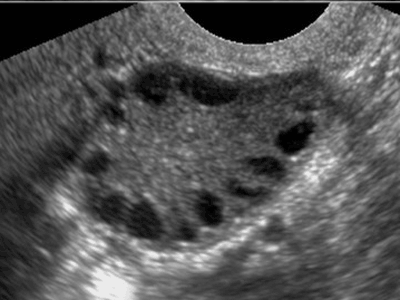

При МФЯ вот:

С доминантным так:

Вот у меня всегда была верхняя картинка. А сейчас он мне делает УЗИ и я вижу нижнюю, третью картинку. У моего врача кстати в кабинете прикольно. Ложишься на кушетку, а у тебя в ногах сверху прилеплен монитор, на котором все отображается. Лежишь, короче, и не напрягаясь смотришь че там как у тебя внутри._)))))